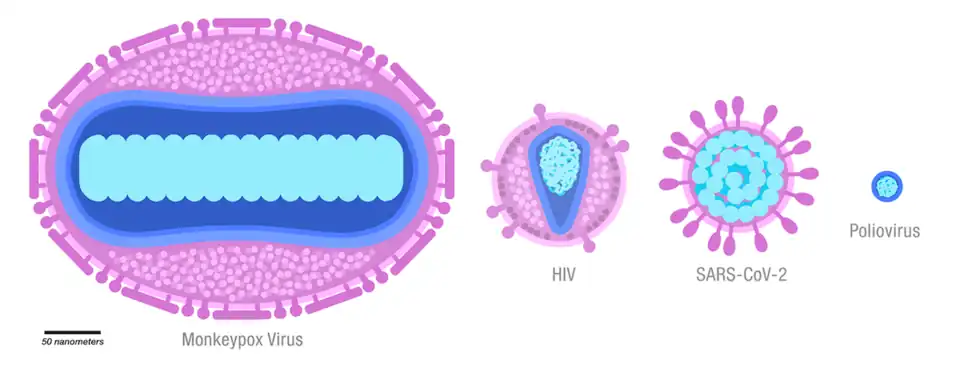

Mpox in both humans and animals is caused by infection with Orthopoxvirus monkeypox – a double-stranded DNA virus in the genus Orthopoxvirus, family Poxviridae, making it closely related to the smallpox, cowpox, and vaccinia viruses.[1]